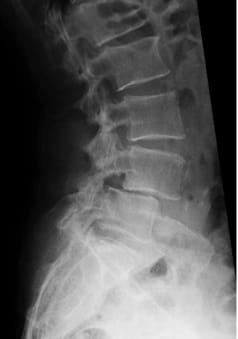

Spondylolisthesis = vertebral slippage between the 4th and 5th lumbar vertebrae, reconstruction and dynamic stabilisation with viscoelastic disc prosthesis and dynamic fixator